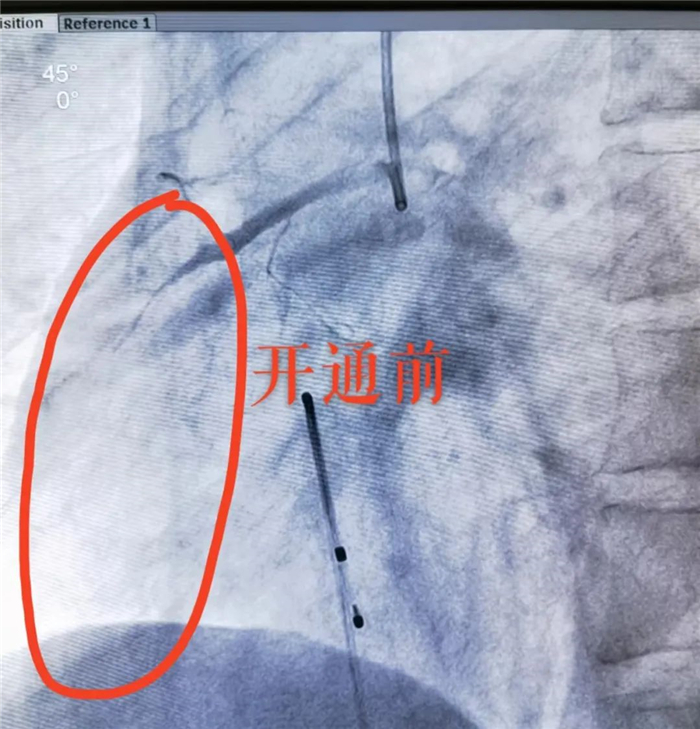

造影显示,患者右冠状动脉完全闭塞、血供中断,这也正是导致其心肌梗死的“罪魁祸首”!

分秒必争!在大家精细操作、紧密配合下。安装临时起搏器保驾,终于为患者顺利打通闭塞血管,使濒死的心肌恢复血供!患者转危为安。转ICU继续监护治疗。该例抢救,从接诊入院到完成手术,仅用时40分钟!